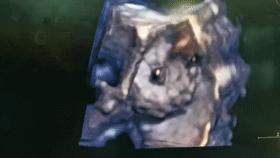

三维超声下“跳动的封堵器”

实时四维超声下“跳动的封堵器”